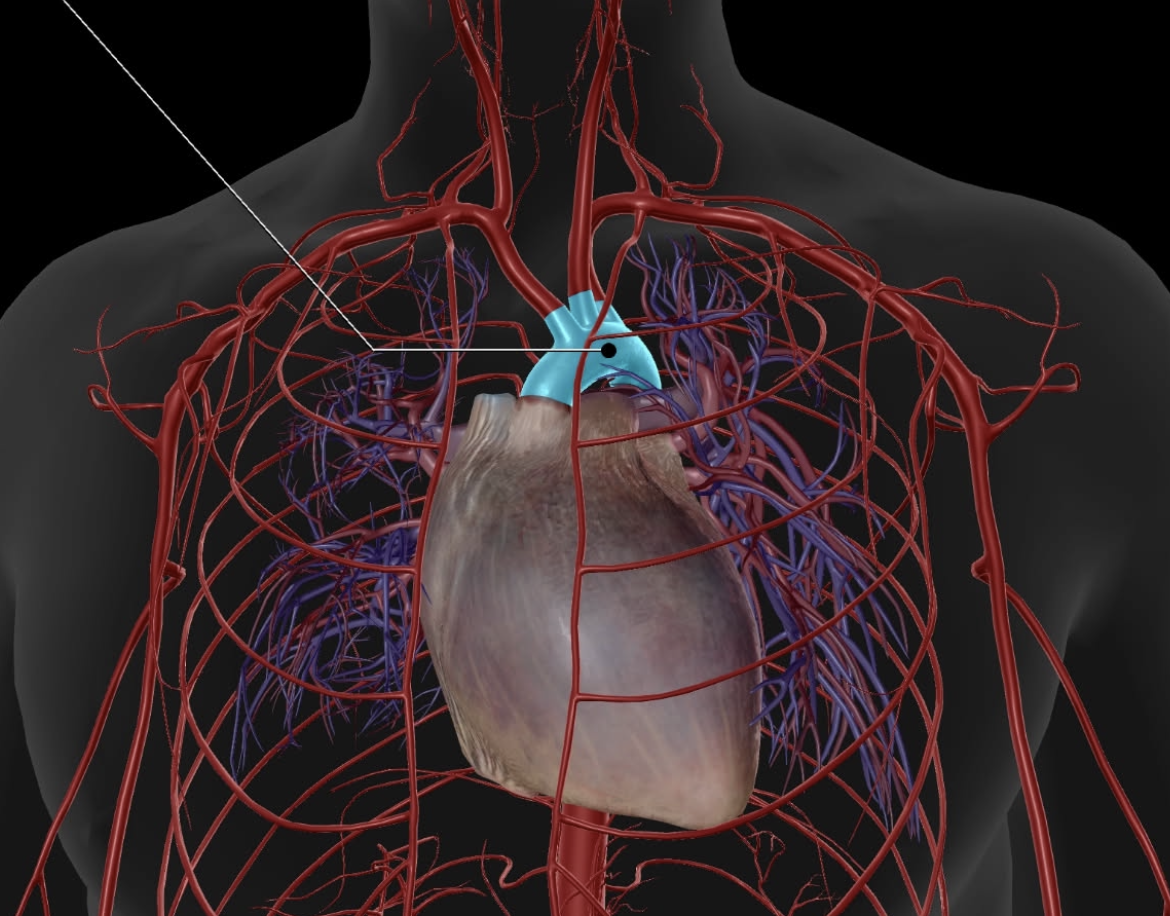

Superior Vena Cava

Pulmonary Trunk

Brachiocephalic Trunk

Brachiocephalic Vein

Pulmonary Artery